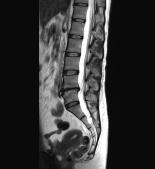

腰椎MR検査

画像コントラストが優れており、骨以外に椎間板や神経も描出することが可能です。